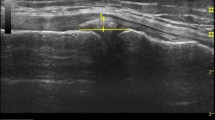

Sonographic evaluation of the postero-lateral meniscal corner was performed using a 5–10 MHz linear transducer in combination with the US unit Sonosite® MicroMaxx® (SonoSite, Inc., Bothell, WA, USA). Images were first acquired in the supine position (unloaded condition) and then in bipedal stance (loaded condition). 10° of knee flexion and 0° of tibia rotation were standard for examination. The optimal transducer position for ME measurement was located in the supine condition and marked to ensure consistent transducer positioning under both loading conditions. US images in the unloaded condition were acquired twice by each observer to determine test–retest reliability. US images in the loaded, standing condition were acquired once by each observer.

To our knowledge, no standardized US examination protocol for lateral ME measurements has been published yet. Therefore, the following approach was adopted to warrant consistency (Fig. 2). First, the fibula head and fibula attachment of the lateral collateral ligament (LCL) were located in the longitudinal plane. Then, the probe was shifted proximally along with the LCL until its femoral attachment appeared in the field of view. In this position, the probe was first pivoted to visualize the femoral origin of the popliteal tendon (PT) and then shifted centrally to the tibiofemoral joint line. With the probe held perpendicular to the joint plane and the tibial cortical rim, the orientation of the probe was slightly adjusted for optimal visualization of the distal lateral femur in combination with the PT, the proximal lateral tibial condyle, and the lateral meniscus in between. This final image was used for ME measurements.

Standardized ultrasound-based examination of lateral meniscal extrusion. a Lateral view of the knee joint depicting the relevant landmarks. b1, b2, c1, c2, d1, d2 Transducer positioning and related ultrasound image for slice 1, 2 and 3, respectively. FH, fibular head. LFC, lateral femoral condyle. LM lateral meniscus. LTC lateral tibial condyle. *, lateral collateral ligament. **, popliteus tendon